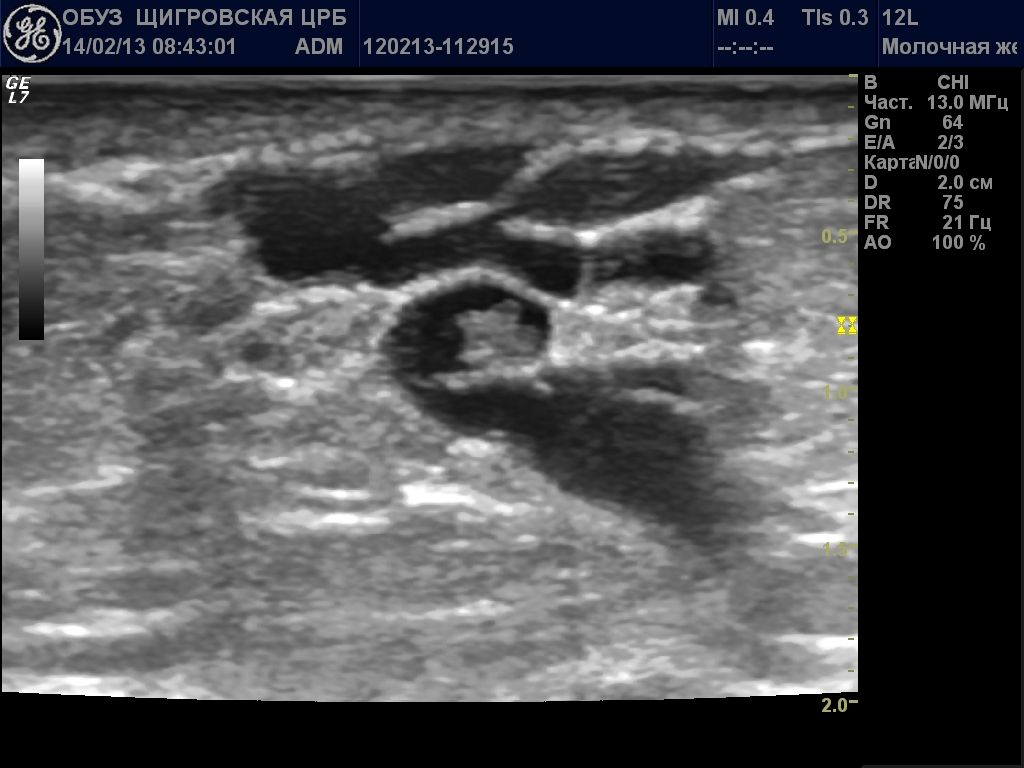

Непременно выполняется ультразвуковое исследование молочной железы. Данный метод достаточно информативен и безопасен. УЗИ помогает выявить размеры новообразования и его структуру. На руки пациенту выдается фото сканирования железы.

- Ультразвуковое исследование.